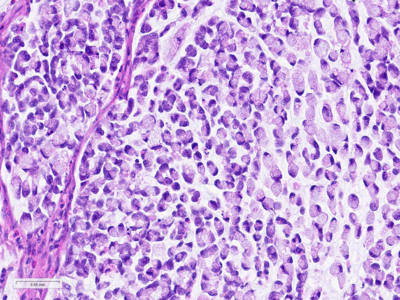

Histologically, the tumour was confirmed to be an adenocarcinoma invading through the gastric submucosa into the muscularis propria (Panel A), showing multiple architectural patterns. While the majority of the lesion displayed a tubular and papillary arrangement of neoplastic cells (Panel B), there were also mucin pools containing floating tumour cells (Panel C), as well as areas of discohesive signet-ring cells (Panel D), so called for their intracytoplasmic mucin droplet that eccentrically displaces the nucleus. The different architectural patterns were not entirely independent of each other nor were they intermingled, but rather arranged side by side (Panel E).